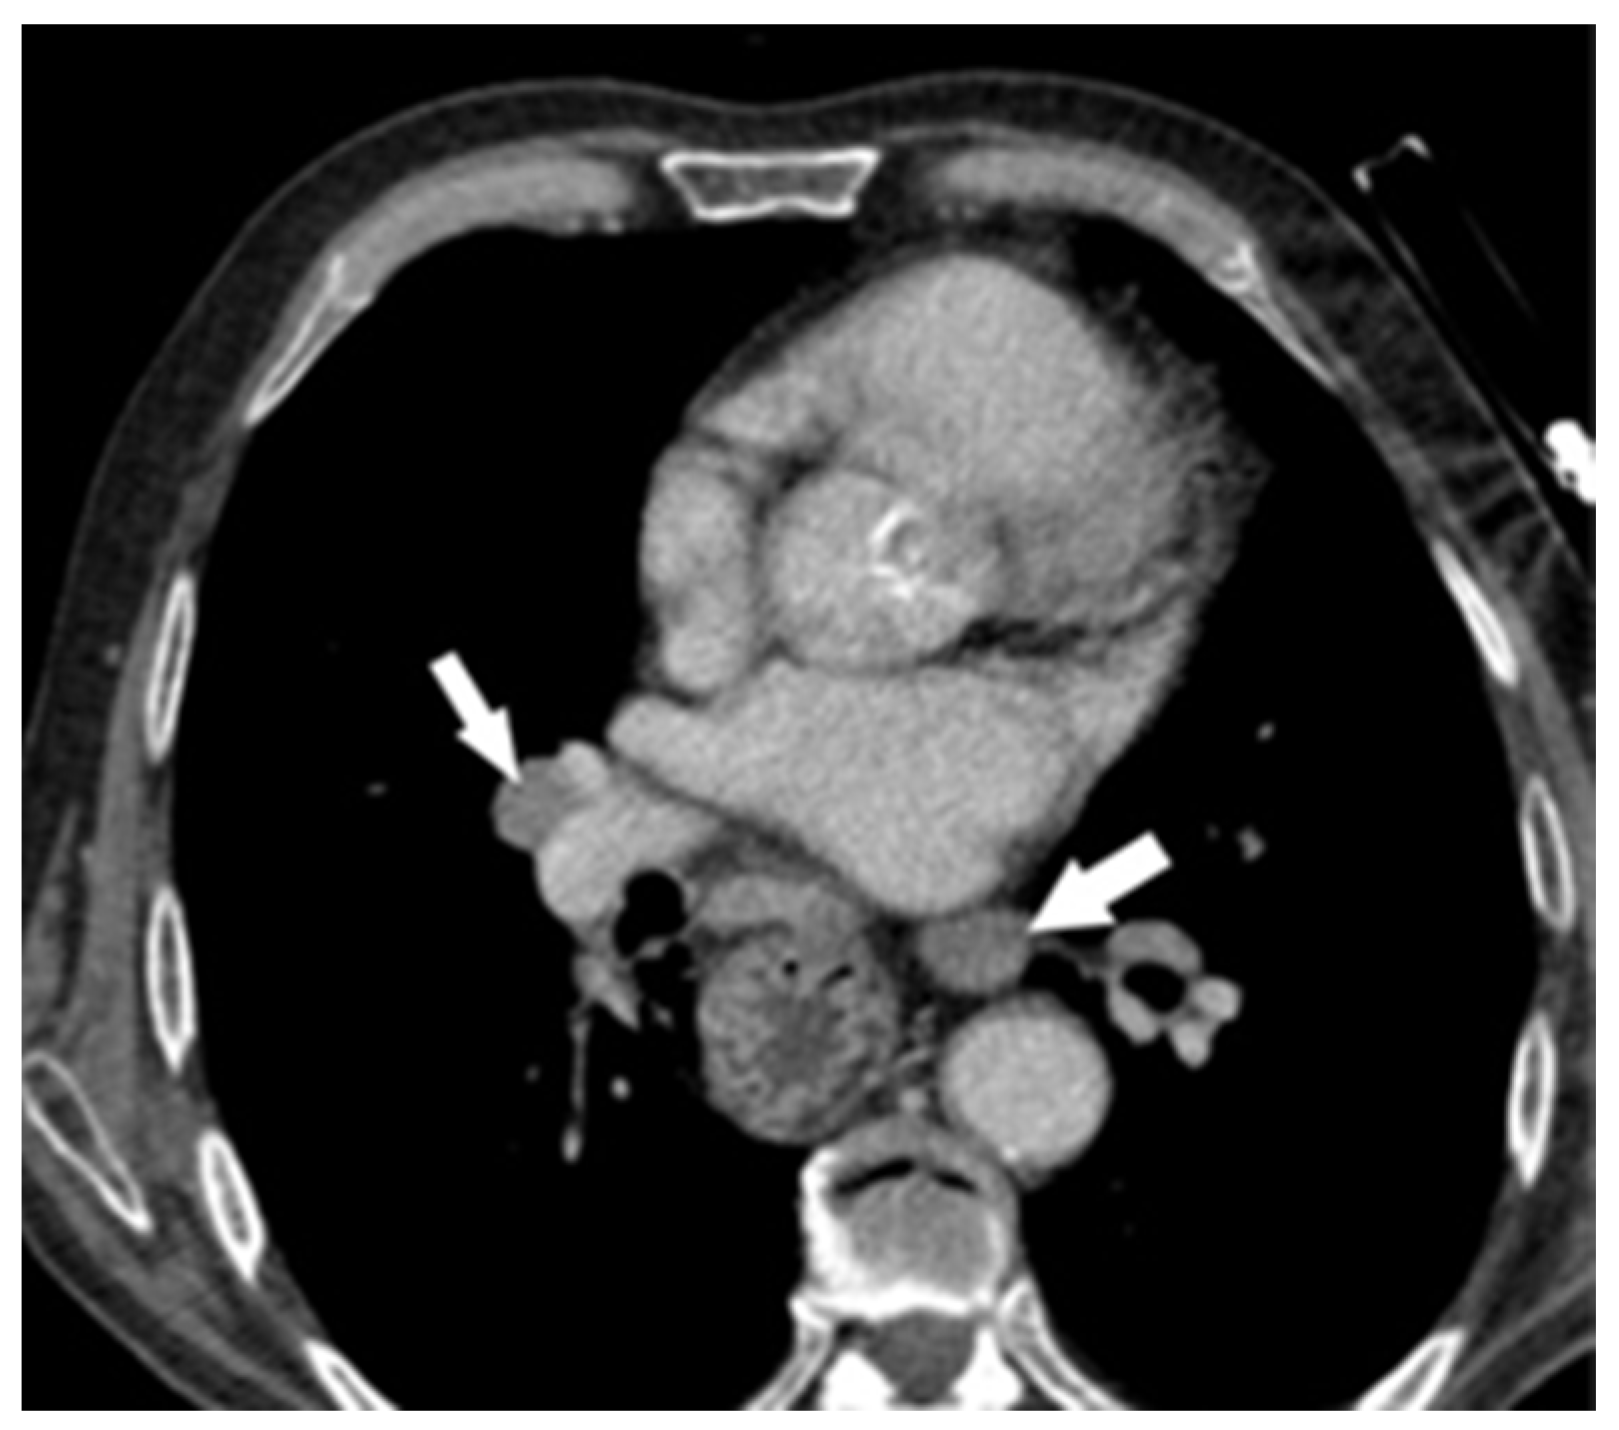

2. Case Report